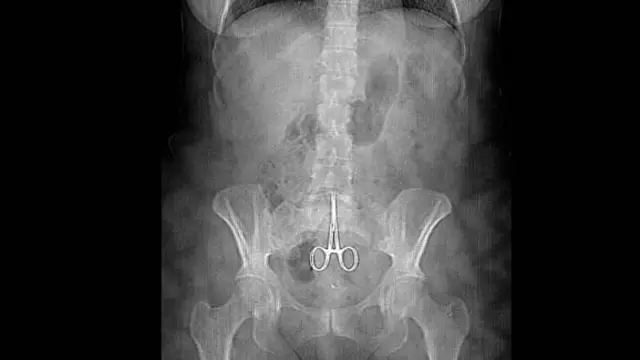

Gunting Operasi Tertinggal di Rahim

Kasus alat operasi yang tertinggal di dalam tubuh pasien banyak terjadi. Salah satu kasusnya menimpa seorang wanita bernama Anne. Wanita yang berasal dari Lyon, Prancis ini mengeluh sakit yang luar biasa pada perutnya setelah lima bulan menjalani operasi di rahim.

Pada 16 Februari 2011, baru diketahui dari hasil foto rontgen bahwa sebuah gunting operasi tertinggal di dalam rahimnya. Akhirnya operasi dilakukan kembali untuk mengangkat gunting tersebut. Rasa sakit yang dialami Anne terjadi karena ujung gunting melukai perut bagian dalam ketika dia terbatuk.